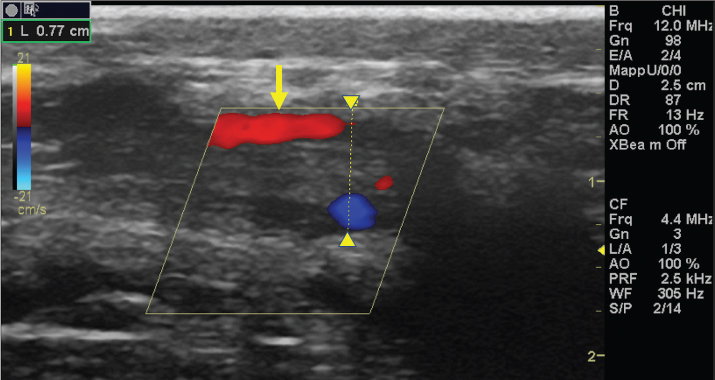

Fig. 2. A 20-G intravenous catheter placed into the right congestive facial vein in the anesthetized horse. The left jugular vein appeared as an anechoic tubular structure which collapsed under the probe pressure, the color Doppler examination revealed normal blood flow within the vessel (Fig. 3). Bi-dimensional ultrasonography of the right jugular vein showed a heterogeneous, non-cavitating, hypoechoic structure occluding a narrowed right jugular vein for about 30 cm of length localized in the proximal and mid-portion of the neck compatible with a thrombus (Fig. 4). The color Doppler examination showed blood flow through the lateral portions of the thrombus in the cranial and mid-portions of the right jugular vein (Fig. 5). Cranially to the thrombus, a marked distension of the maxillary and linguofacial veins was evident, with a turbulent and echogenic flow; the latter was compatible with blood stasis near the thrombus (Fig. 6). Caudally to the thrombus, the right jugular vein presented reduced diameter, thickened walls, and normal blood flow (Fig. 7). The cranial part of the thrombus originated from a heterogeneous scare tissue, localized at the level of the right mandibular angle (Fig. 8). After injection of the first saline contrast bolus in a right facial vein, no microbubbles appeared in the right jugular vein, caudally to the thrombus, proving the presence of a complete right jugular vein occlusion. On the contrary, after injection of the second bolus, microbubbles were visualized in the left jugular vein as small, intense, echo signals within the vein lumen, demonstrating the presence of collateral circulation that drained the blood from the right facial veins to the left jugular vein (Fig. 9). Venography results confirmed the complete occlusion of the right jugular vein and the presence of submandibular venous collaterals that connected the right facial veins with the left jugular vein (Figs. 10 and 11). Based on the previous results, the diagnosis of JVT with complete occlusion of the vessel lumen was confirmed. The horse’s owner refused any proposed medical or surgical therapy.

Fig. 3. Color Doppler image of the normal blood flow in the left jugular vein. Ethical approvalThe publication of this case report was approved by the Institutional Animal Care and Use Committee at the University of Sassari (Comitato Indipendente di Bioetica di Ateneo per la Sperimentazione Animale (CIBASA); protocol number 22865), according to the Italian legislation.